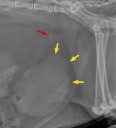

RadioQuiz 36 – Chat enveloppé cherche à faire pipi

Et celui-là, qu’a-t-il ingurgité ?